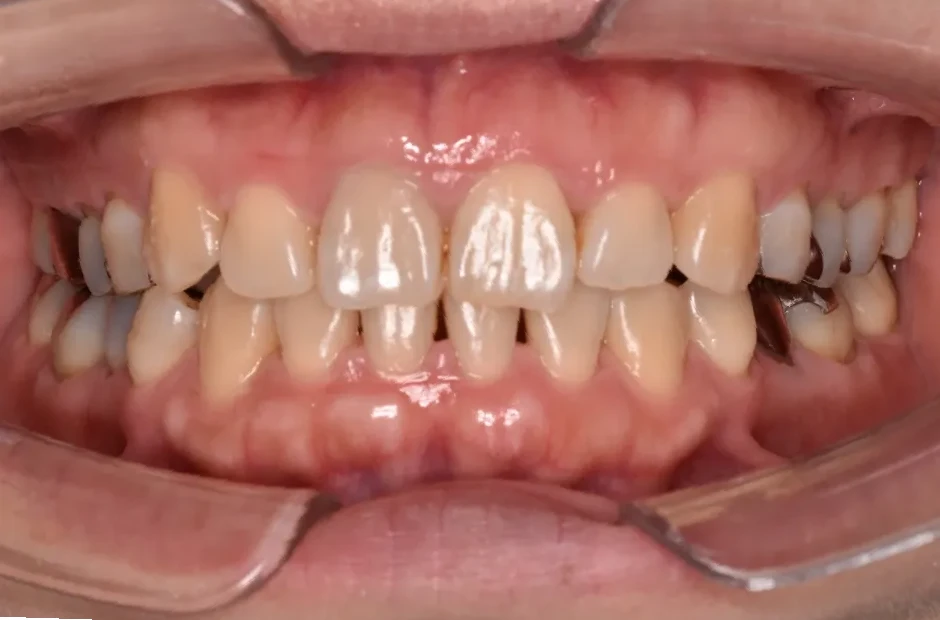

叢生

| 診断名・主訴 | 叢生 |

|---|---|

| 年齢・性別 | 43歳・女性 |

| 治療期間・回数 | 2年7か月 27回 |

| 治療に用いた主な装置 | 舌側矯正 |

| 抜歯部位 | 両顎4,4 |

| 治療費 | 100万円(税抜) |

| リスク・副作用 | 装置による違和感・疼痛・歯肉退縮・歯根吸収・虫歯のリスクなど |

治療後